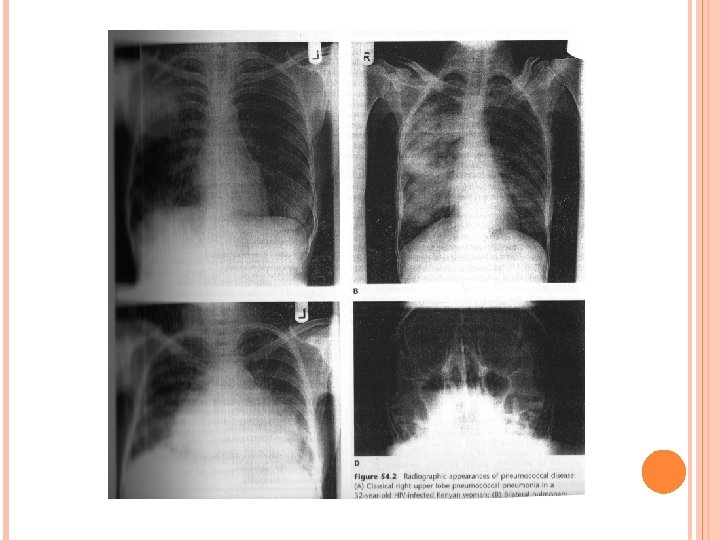

Streptococcus Pneumoniae the pneumococcus, is a ubiquitous human respiratory bacterial phatogen, well know for its association with pneumonia and meningitis.